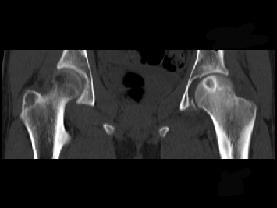

问题 患者,女,19岁,左髋疼痛、活动受限伴跛行6个月,无发热、盗汗病史,曾考虑左髋关节结核并抗结核治疗2周,症状有一定缓解,请结合所提供图像,选择最佳答案 ( )

选项 A、骨化性纤维瘤 B、骨囊肿 C、非骨化性纤维瘤 D、软骨母细胞瘤 E、骨样骨瘤

答案 D